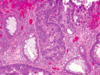

What kind of polyp is this?

- Peutz-Jegher’s syn polyp: large, pedunculated polyps characteristic arborizing network of CT -> smooth muscle, lamina propria and glands lined by normal-appearing intestinal epithelium

- Complex glandular architecture, and presence of smooth muscle are features that distinguish Peutz-Jeghers polyps from juvenile polyps

- Stalk with smooth muscle bands and architectural complexity

- REMEMBER: P-J is auto dom, and characterized by devo of benign hamartomatous polyps in GI tract and hyperpigmented macules on lips and oral mucosa